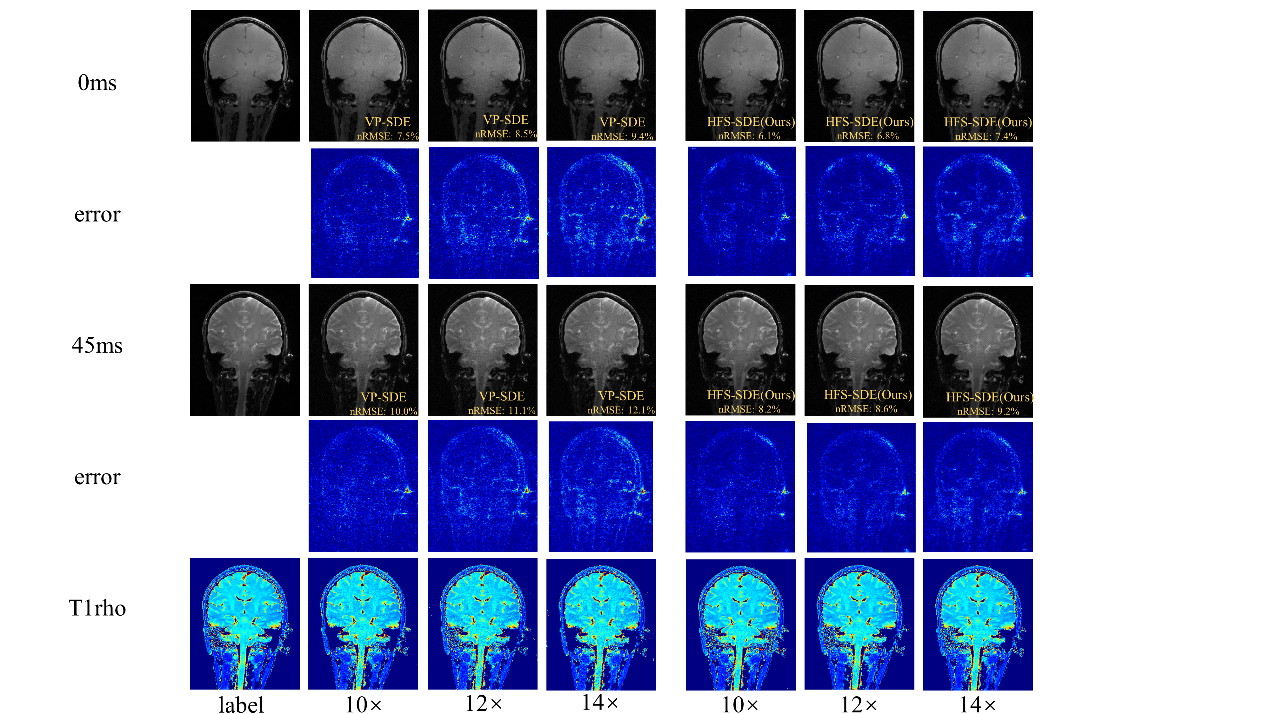

在超高场功能磁共振T1ρ弛豫定量成像方面,团队首次在5.0 T磁共振平台上测试了大脑T1ρ成像的可行性,并比较了使用3.0 T和5.0 T扫描仪所得的T1ρ值。实验结果表明,5.0T下获得了信噪比更高的T1ρ加权图像。在高分辨率成像中,5.0T的信噪比优势更明显。该成果发表在Frontiers in Physics(2022,10:1016932)。团队还提出一种用于基于扩散的MR重建方法——HFS-SDE,并将这种新方法应用于MR T1ρ映射,实现14倍的高加速度,相对于VP-SDE的高速倍数下没有显示伪影,nRMSE值明显优于VP-SDE,并且图像的高频细节得到了更好的重建,该成果“Diffusion generative prior-based highly accelerated MR T1ρ mapping”在2023 ISMRM会议被收录为Power Pitch。

图4 团队提出的HFS-SDE方法不仅提高了扩散模型的稳定性,并在5T时实现了T1ρ定量成像的高加速,而且更准确地恢复MR图像中的高频细节。